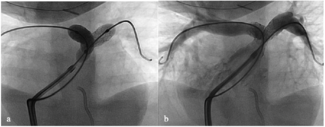

An 83-year-old woman with symptomatic severe aortic stenosis was referred for transcatheter aortic valve replacement. Diagnostic left heart catheterization documented diffuse 3-vessel coronary artery disease.